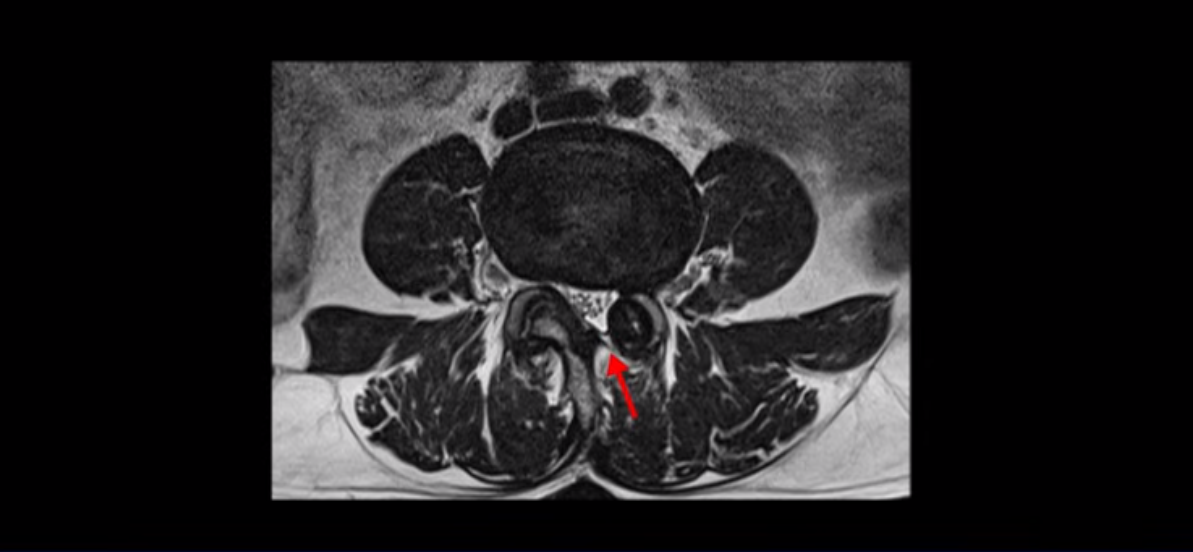

단면으로 보면 왼쪽 후궁을 제거한 흔적이 보입니다.

5번 1번도 왼쪽 후궁을 열고 수술 받았습니다.

이분은 오른쪽, 왼쪽 다리에 모두 방사통이 심하고 왼쪽 다리에 마비 증상, 즉 풋드랍(족하수) 증상이 있습니다. 왼쪽 신경 가지가 빠져나가는 추간공을 보면 두 마디가 좁아져 있습니다.

이런 신경 구멍이 좁아져 있는 걸 협착이라고 합니다.